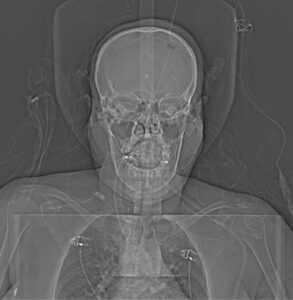

Topogram AP

Topogram Lateral

Topogram Parameters

Topogram (AP)

- Topogram length: 512Ā cm

- Slice: 0.6 mm

- Scanning direction: Craniocoudal

- Tube position: Top

- Stop the topogram scanning when the scanning reach / pass over the arch of aorta

Topogram (Lateral)

- Topogram length: 256Ā cm

- Tube position: Lateral

- Stop the topogram scanning when the scanning reach / pass over the base of skull